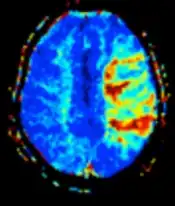

Diffusion weighted (DWI) | Conventional | DWI | Measure of Brownian motion of water molecules.[28] | High signal within minutes of cerebral infarction (pictured).[29] | ![]() |

Apparent diffusion coefficient | ADC | Reduced T2 weighting by taking multiple conventional DWI images with different DWI weighting, and the change corresponds to diffusion.[30] | Low signal minutes after cerebral infarction (pictured).[31] | ![]() | |